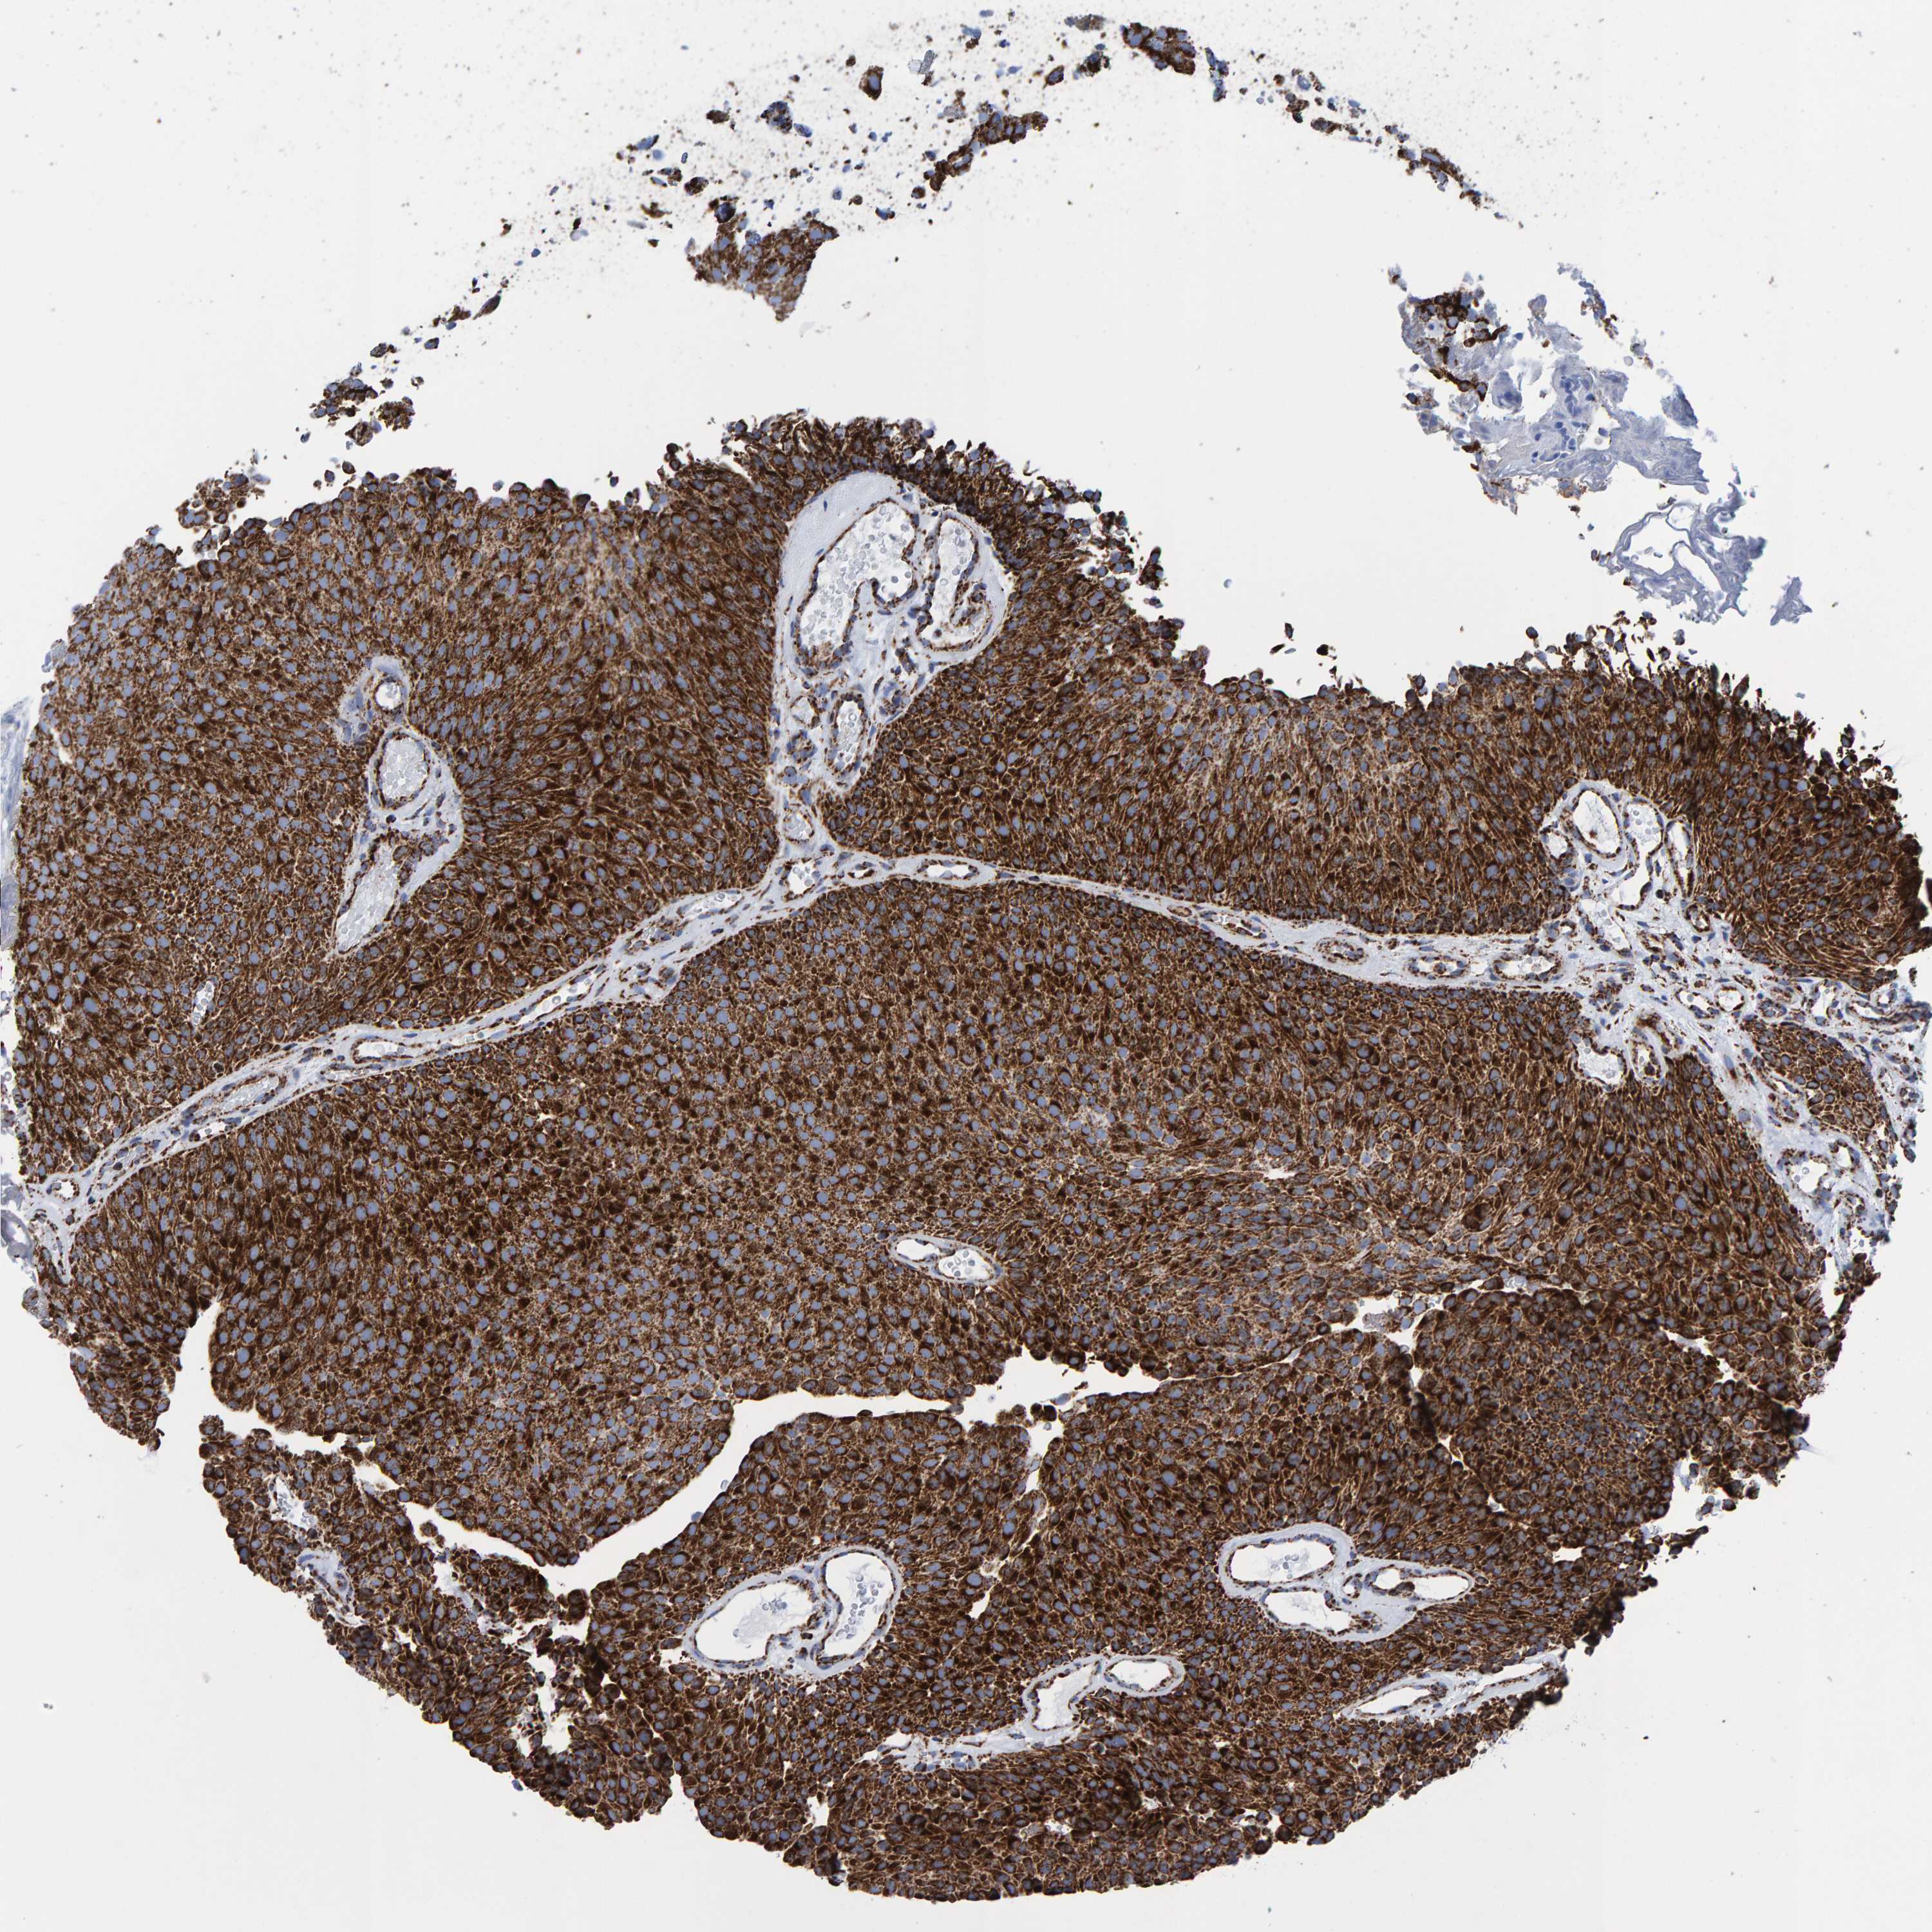

UROTHELIAL CANCER - Protein expressioni

A mouse-over function shows sample information and annotation data. Click on an image to view it in a full screen mode. Samples can be filtered based on level of antibody staining by selecting one or several of the following categories: high, medium, low and not detected. The assay and annotation is described here.

Note that samples used for immunohistochemistry by the Human Protein Atlas do not correspond to samples in the TCGA dataset.

Antibody stainingi

Antibody staining in the annotated cell types in the current human tissue is reported as not detected, low, medium, or high, based on conventional immunohistochemistry profiling in selected tissues. This score is based on the combination of the staining intensity and fraction of stained cells.

Each image is clickable and will lead to virtual microscopy that enables deeper exploration of all samples and also displays staining intensity scores, fraction scores and subcellular localization as well as patient and tissue information for each sample.

Antibody HPA022853

Antibody HPA023043

Antibody HPA023048

Staining

High

Medium

Low

Not detected

Intensity

Strong

Moderate

Weak

Negative

Quantity

>75%

75%-25%

<25%

None

Location

Nuclear

Cytoplasmic/membranous

Cytoplasmic/membranous,nuclear

Urothelial carcinoma, Low grade

Urothelial carcinoma, High grade